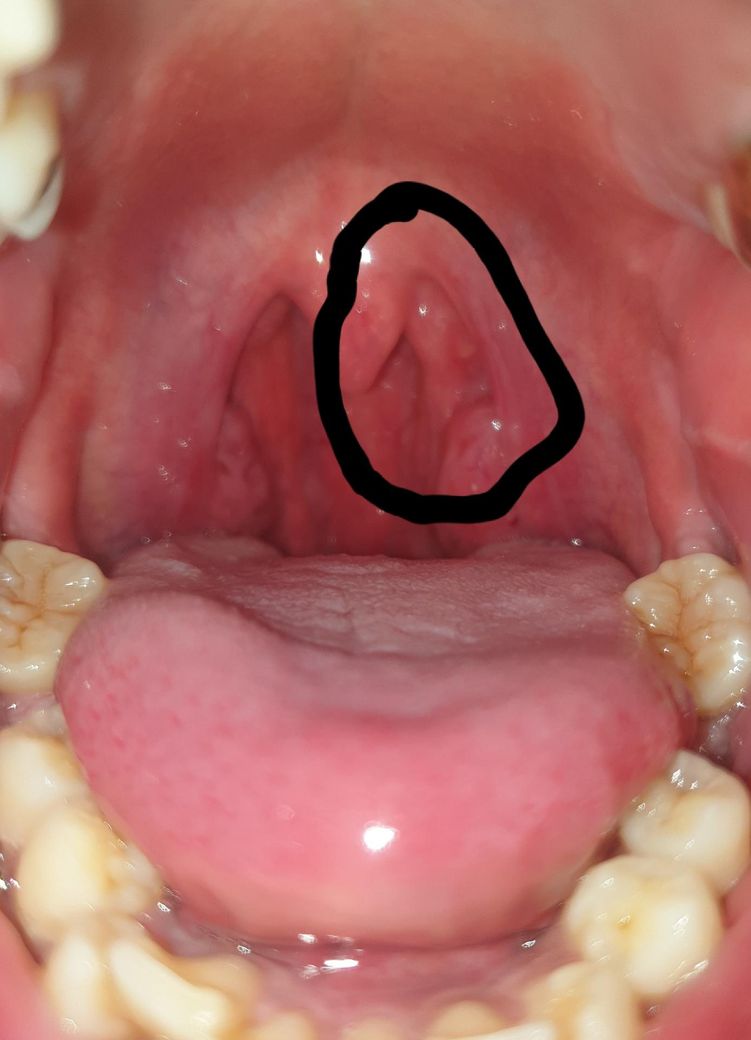

검게 동그라미 친 부분이 생겼어요

목젖뒤에 화상입은거 같은데 위치는 비슷한데

왠지 종양처럼 생겨서 무서워서 올려요

지금 목에 걸리는 느낌이 나서 찍었더니 이렇게 나왔네요

• 뜨거운 음식 이후 3일 경과 후 통증과 이물감이 발생했다는 점을 고려하면, 현재 병변은 구강 및 인두 점막의 열손상에 따른 염증과 부종으로 설명되는 경우가 가장 많습니다. 인두 점막은 열에 취약하여 손상 후 일시적으로 부풀어 오르거나 덩어리처럼 보일 수 있으며, 특히 목젖 뒤쪽은 해부학적으로 변화가 더 두드러지게 관찰되는 부위입니다. 통증이 동반되고 비교적 급격히 생겼다는 점도 외상성 병변의 특징에 부합합니다.

종양의 경우 일반적으로 수주에서 수개월에 걸쳐 서서히 커지며 초기에는 통증이 없는 경우가 많기 때문에, 현재처럼 명확한 원인 이후 단기간 내 발생하고 통증이 동반된 양상은 종양 가능성을 낮추는 요소입니다. 따라서 현 시점에서는 악성 또는 종양성 병변보다는 염증성 변화로 보는 것이 타당합니다.

대부분의 점막 화상은 약 5일에서 10일 사이 점차 호전되며, 2주 이내 자연 회복되는 경우가 많습니다. 자극적인 음식이나 뜨거운 음식은 피하고, 충분한 수분 섭취와 함께 필요 시 소염진통제를 사용하는 정도의 보존적 치료가 적절합니다.

다만 병변이 1주에서 2주 이상 지속되거나 크기가 커지는 경우, 출혈이나 궤양이 심해지는 경우, 삼킴 곤란이 악화되는 경우에는 이비인후과에서 내시경으로 직접 확인하는 것이 필요합니다.